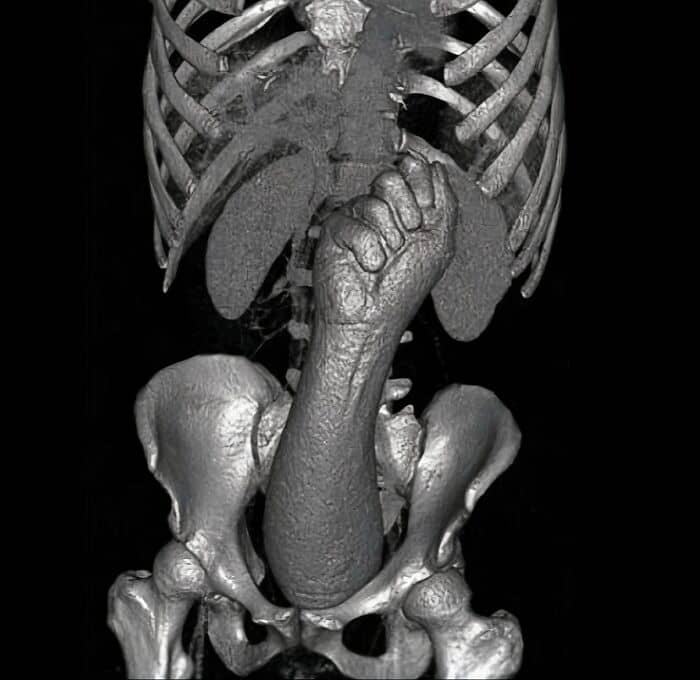

#58 Thanks, I Hate This X-Ray